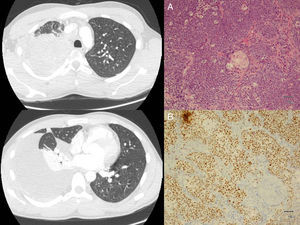

We report the case of a 23-year-old man, smoker of about 10 cigarettes/day, who presented in our hospital with a 2-week history of pain in the right hemithorax radiating to the shoulder, and asthenia. Computed tomography (CT) showed increased density without air bronchogram occupying the posterior and apical segments of the right upper lobe (RUL) with amputation of the corresponding segmentary bronchi, paratracheal mediastinal lymphadenopathies, and significant right pleural effusion (Fig. 1). Given these findings, a positron emission tomography (PET) was performed, revealing a metabolically positive mass in the RUL, with extensive pleural involvement in the same side, mediastinal lymph node involvement, and bilateral supra/infraclavicular lytic bone lesions and metastasis. Fiberoptic bronchoscopy revealed complete stenosis of the posterior and apical segments of the RUL bronchus due to thickened, hypervascularized mucosa, possibly of a neoformative origin. Diagnostic confirmation was obtained from a pleural biopsy obtained by thoracoscopy. The pathology report described a neoplasm formed of nests of undifferentiated cells, and, along with this cell population, abrupt areas of squamous differentiation. The undifferentiated tumor cells showed positive immunoreaction to NUT antibody and pancytokeratin (Fig. 1).